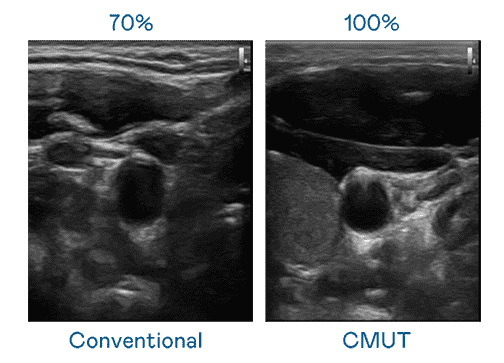

CMUT 技术是一种用电容式微机电元件来产生超音波讯号的技术。。。与传统 PZT 压电式技术相比,,,,CMUT 频宽增加 30%,,,更宽频的超音波讯号让影像解析度大幅提升,,,是实现高影像品质医疗超音波扫描、、、、促进精准医疗发展的关键技术。。

大频宽带来超清晰影像

超音波影像的解析度高低,,,,首先取决于探头能发出的讯号频宽。。。JDB电子 CMUT 可提供高清晰的超音波讯号,,,提供高频宽、、、、高灵敏度、、影像纹理细节更高的超音波影像,,协助医护人员缩短影像判读时间及利用精准的医疗影像进行诊断。。。。